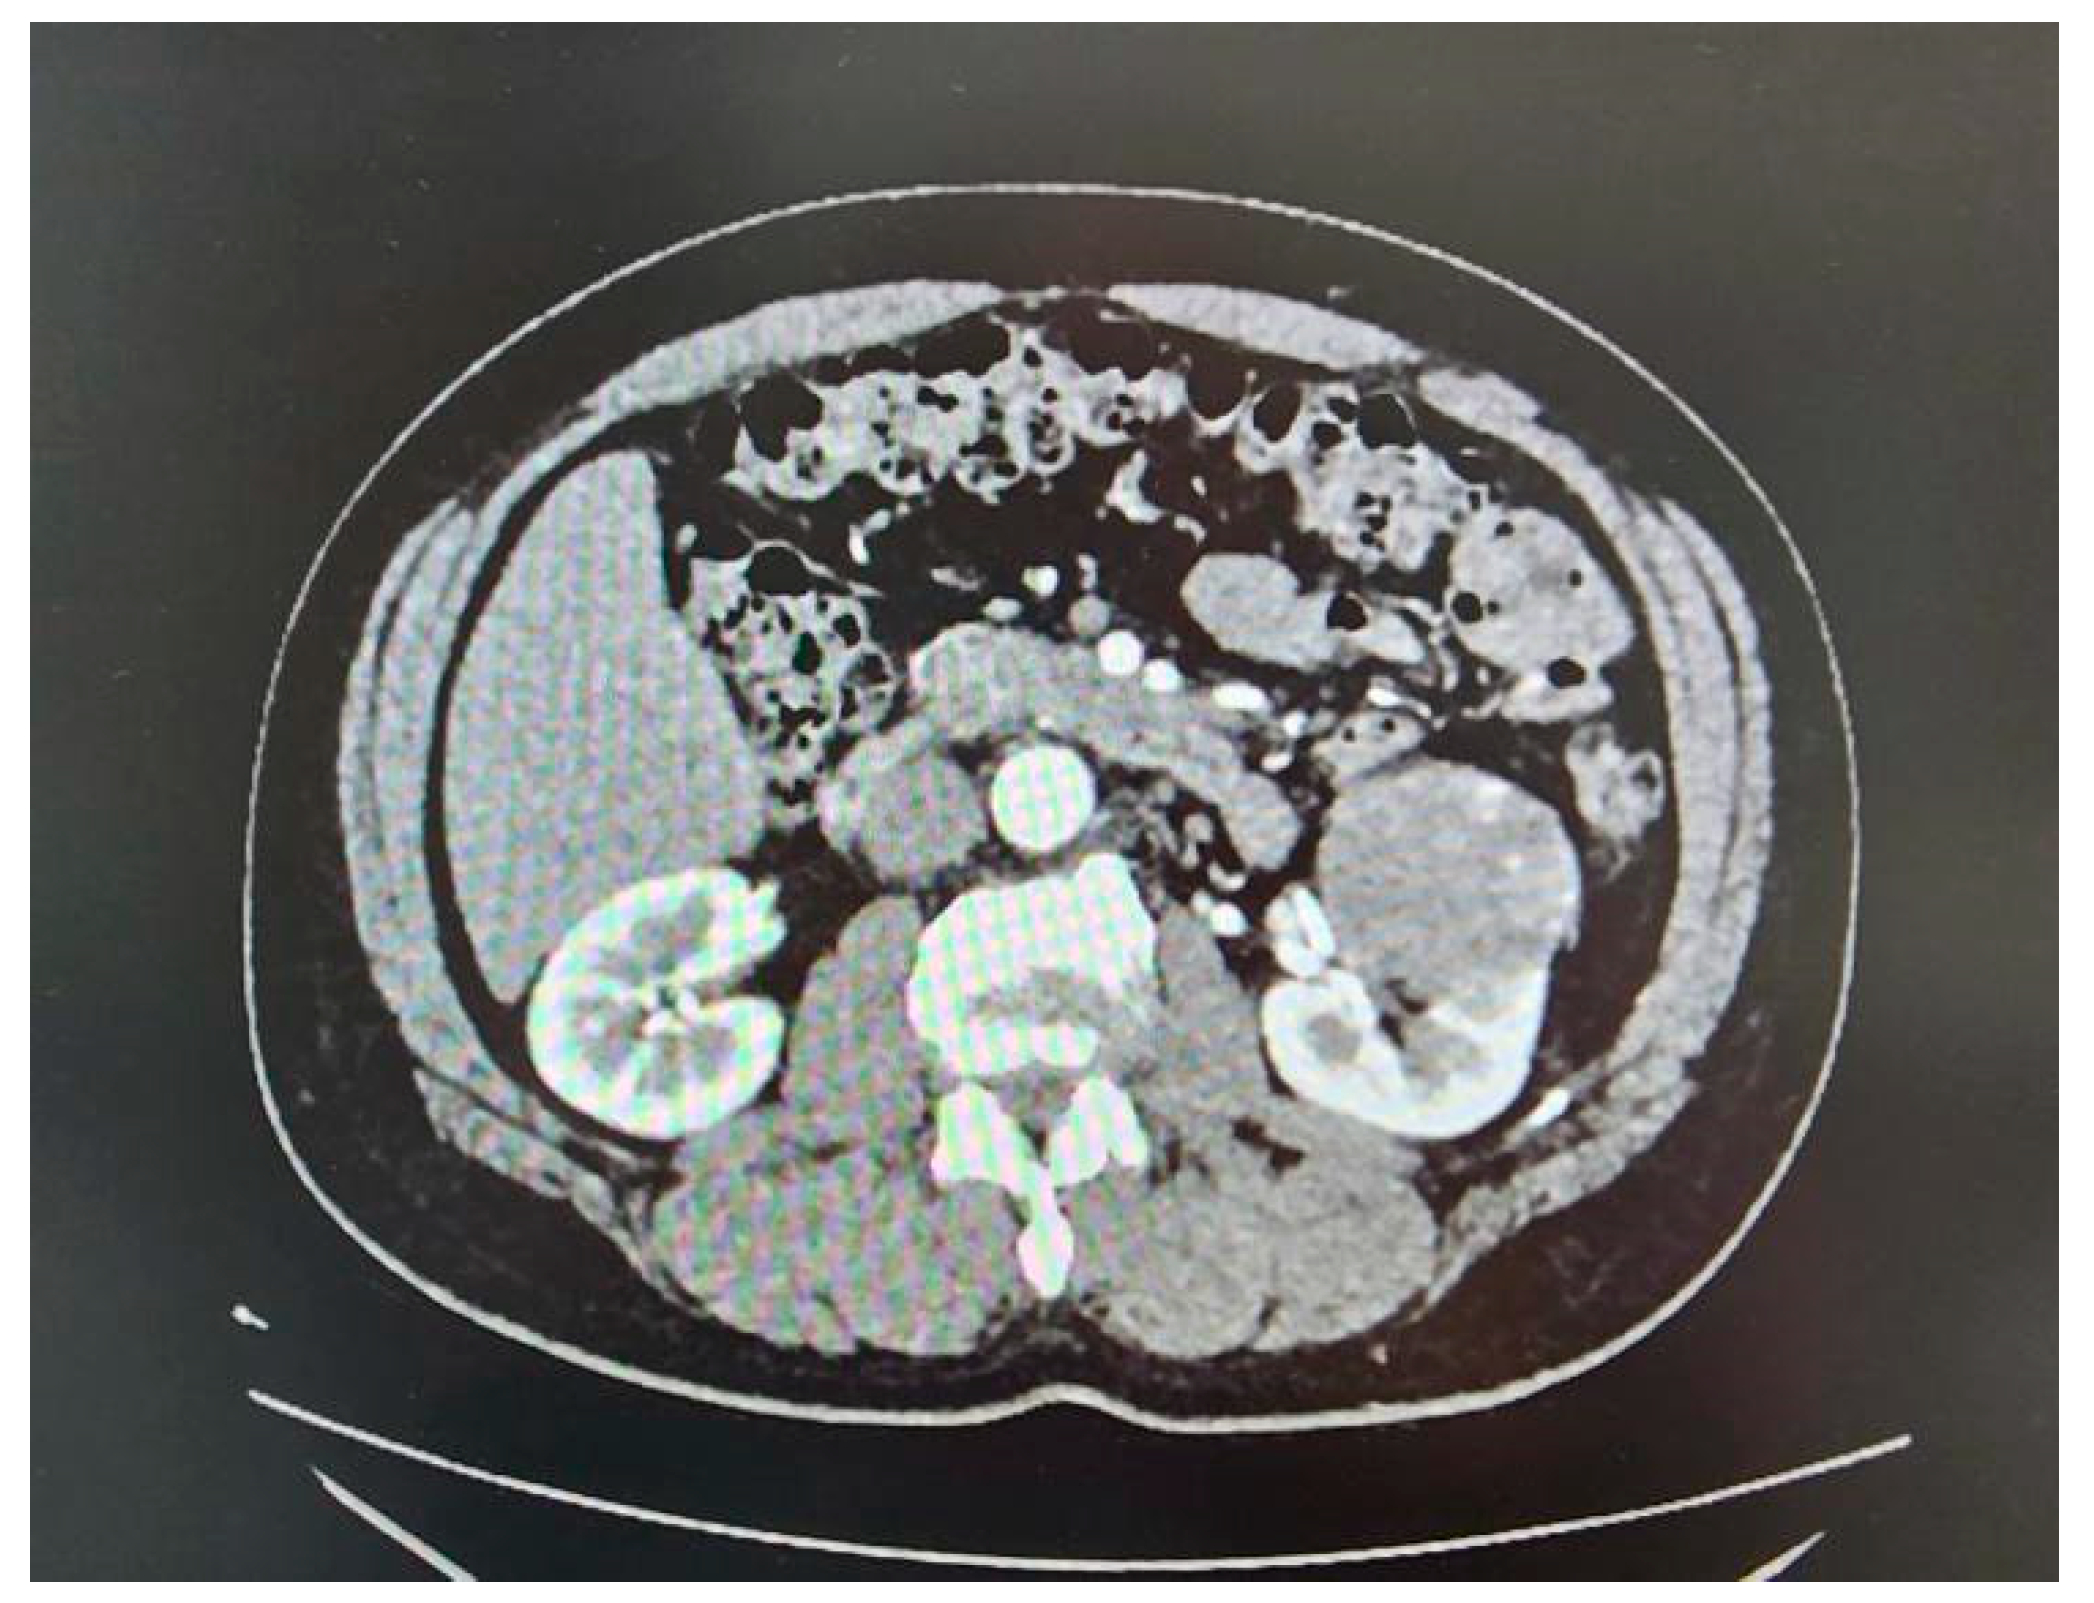

A total of 35 patients, comprising 21 males and 14 females with a mean age of 53.37 ± 15.52 years, underwent RAPN during the study period (Table 1). Tumour characteristics are summarized in Table 2, and perioperative outcomes are detailed in Table 3 and Table 4. All patients had high-complexity tumours, with a median RENAL nephrometry score of 10 (Figure 3A, Figure 3B and Figure 3C).

Figure 3B. Nephrometry score of 9p was given based on the following criteria (R)adius (1 point); (E)xophytic < 50% (2 points); (N)earness < 4mm (3 points); (P)posterior; and (L)ocation relative to polar lines (3 points)